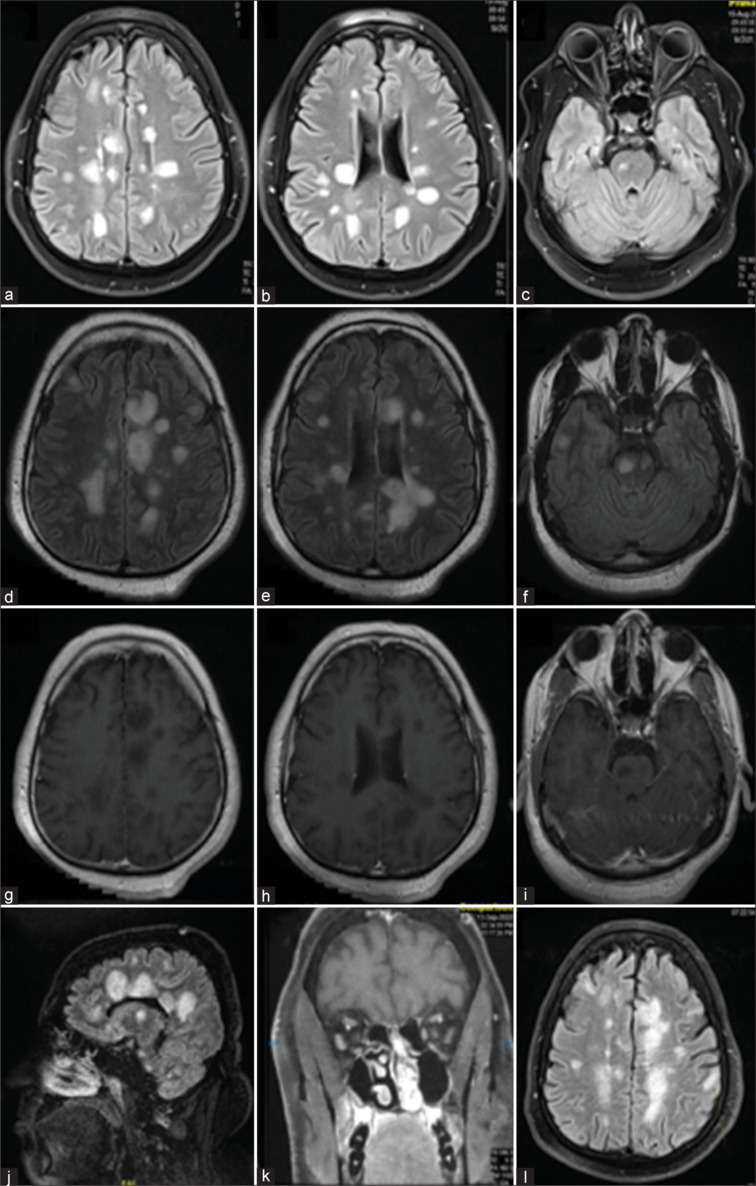

马尔堡病是多发性硬化症(MS)的一种致死性变异,其特点是病程暴发性、快速进展的单相病程,通常导致患者在发病数周内死亡。由于其罕见性,没有确定的治疗指南。我们报告一位34岁的男性,他被诊断为多发性硬化症,磁共振成像显示大量的幕上和幕下白质斑块。类固醇脉冲治疗、静脉注射免疫球蛋白和血浆置换无效。在排除其他鉴别诊断后,考虑马尔堡变异型多发性硬化症,并静脉注射环磷酰胺和甲基强的松龙。患者表现出显著和快速的临床改善,进一步证明环磷酰胺是治疗这种MS变体的有效治疗方式。

Marburg's disease is a fatal variant of multiple sclerosis (MS), distinguished by its fulminant, rapidly progressive monophasic course that often leads to patients' mortality within weeks of onset. Owing to its rarity, there are no established treatment guidelines. We present a 34 year-old male who was diagnosed with MS, and magnetic resonance imaging revealed numerous supra- and infratentorial white matter plaques. Steroid pulse therapy, intravenous immunoglobulin, and plasma exchange were ineffective. After excluding other differential diagnoses, Marburg's variant MS was considered, and intravenous cyclophosphamide with methylprednisolone was administered. The patient showed significant and fast clinical improvement adding to the evidence that cyclophosphamide is an effective therapeutic modality for treating this MS variant.